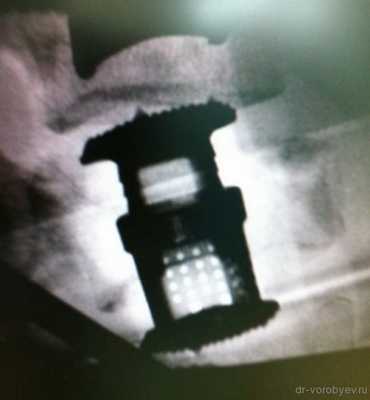

Представлены КТ пациента до и после оперативного лечения по поводу осложненного перелома пятого шейного позвонка. Выполнена корпорэктомия пятого шейного позвонка с комбинированным корпородезом аутокостью из подвздошного гребня и пластиной китайского производства.

Импланты шейного отдела позвоночника на рентгене.

Установка металлической конструкции.